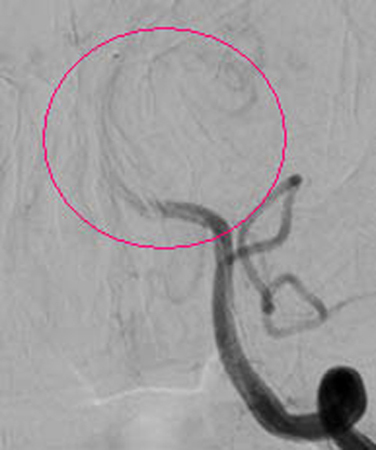

红圈内血管完全闭塞

红圈内所示为经动脉接触溶栓后,血管再通。 7月21日上午,在我院神经外科医护人员的团结协作下,成功完成一例急性脑梗塞介入动脉溶栓手术,该项手术的成功开展,使我院急性溶栓技术达到了新的高度,为全市人民带来福音。 患者张大妈,今年77岁,因“晨起洗脸时突发昏迷1个小时”急诊送入我院,行头颅CT示:排除脑出血、脑梗塞可能。神经外一科9:40接急诊内科紧急会诊通知,王和平医生9:45赶到急诊内科,在了解了病人的一般情况后,考虑患者来院比较及时,还在动脉溶栓时间窗内,遂急诊介入行全脑血管造影,明确为基底动脉完全闭塞(此病致死率高达90%),继而予尿激酶行基底动脉内接触溶栓!之后行造影明确,基底动脉通畅、显影(造影图片见后)!当天下午,患者神志基本清醒,竟然向医生提出要求:要求回家给儿孙做饭。 急性脑梗塞,超早期(起病3小时内)的静脉溶栓治疗是传统的药物治疗,称为“黄金三小时”。但绝大多数患者在该时间段内来不到医院,或是到了医院还来不及明确诊断。但动脉溶栓可将该时间段延长至6-8小时(前循环),后循环血管闭塞甚至可延长到24小时。并且,动脉溶栓目的性更强(直接将溶栓药物灌注在血栓上),全身副反应更小,效果更好。这样就为本类患者的救治提供了机会! 随着2012年我院成为国家卫计委的脑卒中筛查与防治基地,我院对脑卒中的诊断与治疗水平有了进一步的提高。尤其是2013年新型飞利浦数字血管减影机投入临床使用,神经外一科的脑血管介入治疗水平又有了质的飞跃。目前神经外一科常年开展的脑血管病业务有:脑动脉、颈动脉狭窄支架成形术、脑动静脉畸形栓塞术、脑动脉瘤栓塞术、颈内动脉-海绵窦瘘球囊封堵术、急性脑梗塞动脉溶栓术、急性脑梗塞动脉取栓术。 脑卒中防治知识链接:脑卒中非常凶险,像斯大林、丘吉尔这样的名人就是死于脑卒中。如今脑卒中成为了我国人民群众生命健康的“第一杀手”,引起了我国患者与医生的关注。脑卒中即人们常说的“中风”,是严重威胁人类生命健康的常见病。其特点是突然起病,出现脑部功能受损的症状。病人出现肢体瘫痪、感觉异常、语言障碍甚至昏迷、死亡,其致残率和死亡率都非常高。 脑卒中分为两大类:一是脑血管破裂出血,通常称为“脑溢血”,如高血压脑出血、蛛网膜下腔出血等;另一类为血管闭塞导致脑缺血、脑组织坏死,即通常所说的“脑梗塞”。目前脑梗死是我国最常见的卒中类型,占70%以上。(王和平) |